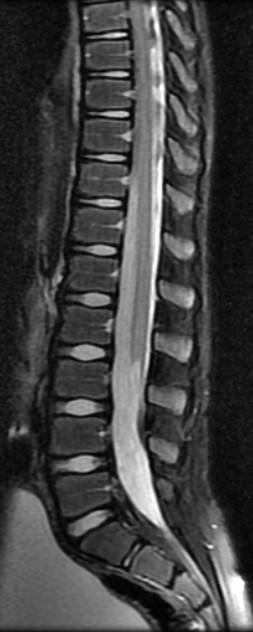

• Normal Conus Position:

• Conus ascends in canal due to faster spinal bone growth

• 24 weeks L3

• 40 weeks inferior L2

• 3 months mid L2 >90%

CSD: WITHOUT MASS SIMPLE

• “Tethered Cord”

• Intraspinal Lipoma/Transitional LMC

• Filum Fibrolipoma

• Tethered Low Lying Cord